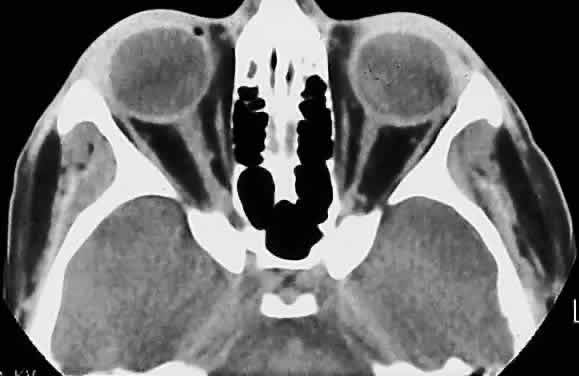

Hypoplasia of the optic nerve is also rare but is more common than aplasia (Figs. 13 and 14). It represents one of the most important developmental abnormalities of the eye and is increasingly recognized as a significant cause of visual deficit in children. Congenital nerve hypoplasia is a nonprogressive condition associated with a reduction in the number of retinal ganglion cells and axons. It may be either unilateral or more commonly bilateral and may involve the entire nerve or be segmental. Although a hypoplastic optic nerve is usually idiopathic, an increased incidence has been noted in the offspring of diabetic mothers and with the maternal use of phenytoin, quinine and, alcohol. Rare reports of an inherited disorder may be found in the literature. Although it may be an isolated abnormality, the hypoplasia is frequently associated with other anomalies—both ocular and nonocular. Additional ocular abnormalities include microphthalmos and congenital nonattachment of the retina. The most common nonocular abnormalities associated with congenital optic nerve hypoplasia include midline CNS structural defects, including septo-optic dysplasia of the septum and ectropia of the posterior pituitary, producing diabetes insipidus.

Fig. 13. Hypoplasia of optic nerve (hematoxylin and eosin staining). Note lack of formation of optic disc tissue.

Fig. 14. Computed tomographic scan of head, showing hypoplastic left optic nerve.

In optic nerve hypoplasia, the optic disc appears gray and is about half its normal size but retinal vessels are present because the optic stalk is invaginated by mesoderm. The optic foramen is also small. Clinically, there may be strabismus, nystagmus, and decreased visual acuity. Severe cerebral abnormalities may be present but the hypoplastic nerve may be the sole abnormality.